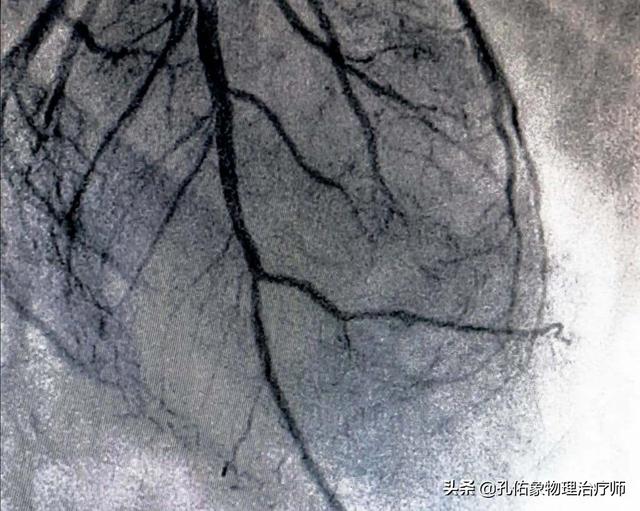

1.冠動脈造影は確かに冠動脈疾患の診断のゴールドスタンダードであり、冠動脈の様々な枝の狭窄病変の位置を明確に同定し、その範囲と血管全体の血液供給を推定できる動的検査である。しかし、この検査は大腿動脈または橈骨動脈を経由して行わなければならない侵襲的な検査であり、検査費用が相対的に高くつくので、この検査を受けるのに適さない患者もいる。

冠動脈造影は確かに信頼性が高く、精度の高い検査である。しかし、血管に損傷があれば、より多くの造影剤を注入する必要があり、ガイドワイヤーによる冠動脈の刺激は冠動脈の血管攣縮のリスクを高めることにつながるという欠点もある。

まず、冠動脈造影は単なる検査であり、冠動脈疾患の重症度を評価し、冠動脈疾患の治療効果を評価し、冠動脈疾患の有無を確認するための重要な検査であることを明確にしなければなりません。そのため、冠動脈疾患と診断された多くの患者さんにとって、冠動脈疾患の治療効果を明らかにするため、また冠動脈疾患の重症度を評価するために、冠動脈造影検査を選択し、状態を評価し、治療を指導しなければならないことがよくあります。